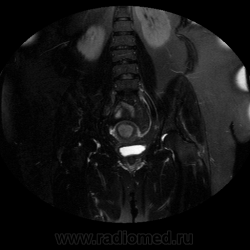

МРТ-органов малого таза.

Пациентка 50 лет,  в анамнезе: Рак шейки матки T2,No,Mo. , с проведением лучевой терапиеи в 1999г. Направлена гинекологом на дообследования для исключения рецидива.

Предположу что это: rec cr coli uteri с переходом на тело матки. Лимфатических узлов не видно, жидкости тоже нет.Стенка мочевого пузыря утолщена (постлучевой цистит).

Пациентке было проведено гистологическое выскабливание по результату низкодифференцированный рак. В данном случае не совсем понятно для меня, расценивать как рецидив или отдельно не зависимо что было в прошлом, эндометриоидный рак,  поскольку изменения МР-сигнала миометрия идет через всю толщину и как видно в полости матки тумор.

Расширение эндометрия, неоднородный сигнал от него , снижена зональная дифференцировка  в области дна-похоже на рак эндометрия.